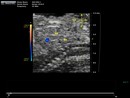

Caption: Ultrasound imaging of mutant 464-003-NA reveals aortic reverse blood flow (details)

Represented Alleles:

b2b464Clo, Mutant line 464; Bench to Bassinet Program (B2B/CVDC), mutation 464 Cecilia Lo

Copyright: This image is from the Laboratory of Dr. Cecilia Lo, a member of the Cardiovascular Development Consortium (CvDC), Bench to Bassinet (B2B) program of the National Heart Lung and Blood Institute (NHLBI), and is displayed with the permission of the authors. J:175213

Caption: Ultrasound imaging of mutant 464-003-NA reveals aortic reverse blood flow in diastole (details)

Caption: Ultrasound imaging in transverse view of mutant 464-003-NA reveals hypoplastic left ventricle (LV) (details)